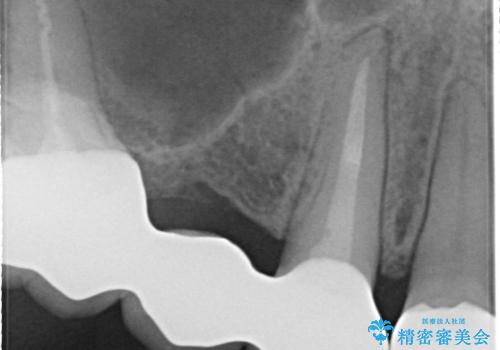

- 全体的な治療と、見た目をきれいにしたとのご希望で来院されました。

上顎の前歯はガタガタがあり、過去に治療した歯はつぎはぎのようになっており、審美的に周囲と調和がとれていない状態でした。

治療計画としては

①仮歯を装着

②矯正治療

③セラミック装着

の順で行いました。